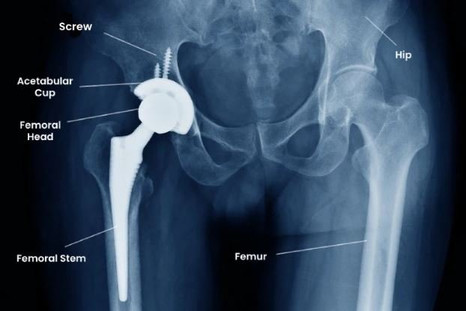

During my interview with Dr. Ponnanna, he emphasized that for many patients suffering from severe hip arthritis, debilitating pain or loss of mobility, total hip replacement can transform daily life. The benefits, he explained, often include:

- Pain relief: Replacing a worn-out hip joint with a prosthetic one tends to relieve chronic pain due to arthritis or joint degeneration.

- Improved mobility: Many patients regain the ability to walk, climb stairs, sit comfortably — activities that may have been painful before surgery.

- Better quality of life: For individuals whose work, daily tasks, or lifestyle are hindered by hip pain, restoring joint function can mean returning to a more active and independent life.

- Long-term joint preservation: With modern techniques and proper rehabilitation, a well-implanted prosthetic joint may last many years, helping avoid further deterioration.